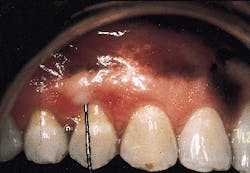

A nonresorbable membrane for GTR was placed over the defect as seen in Photograph #4. The membrane was composed of e-PTFE and was obtained from the W.L. Gore Co. in Flagstaff, Ariz.

Photograph #4: An expanded polytetrafluorethlyne membrane was placed over the root surface and secured. The facial flap was then sutured over the membrane.